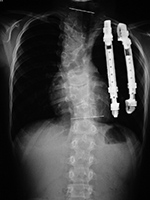

These are two examples of VEPTR-VEPTRII Vertical Expandable Prosthetic Titanium Rib (DePuy Synthes). © DePuy Synthes 2016. All rights reserved. VEPTRII™ is a trademark of DePuy Synthes. |

TIS devices devices are designed for skeletally immature patients who have severe, progressive spinal deformity or thoracic deformity and who are at risk for developing thoracic insufficiency syndrome in which the thorax and spine cannot support normal respiration or lung growth. This includes patients with progressive congenital, neuromuscular, or idiopathic scoliosis (figure: congenital spinal deformity and expandable ribs). Such devices expand the rib cage or slow progressive deformity of the thorax by mechanically stabilizing the thorax and distracting a portion of the rib cage. TIS apparatus consists of rib to rib, rib to spinal lamina, or rib to pelvis expandable bars which can adjust to patient growth (figure: TIS devices). There is limited experience with the use of expandable ribs and similar devices. There does seem to be a high rate of complications, and it is possible many patients with congenital scoliosis may do well with advanced bracing rather than spinal or thoracic cage surgery (Weiss, 2016).